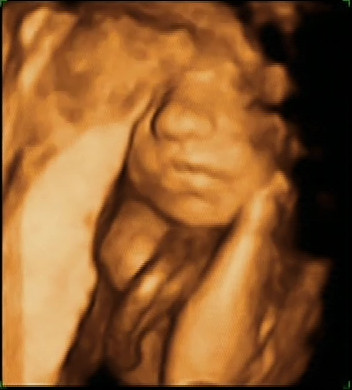

maar al snel had hij het door dat we aan het kijken waren en begon ontdeugend te lachen

om daarna verlegen weg te kruipen.

Awesome.